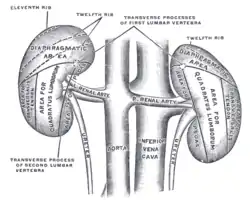

Volume rendered CT scan of abdominal and pelvic blood vessels. The posterior surfaces of the kidneys, showing areas of relation to the parietes.

The posterior surfaces of the kidneys, showing areas of relation to the parietes. Renal artery